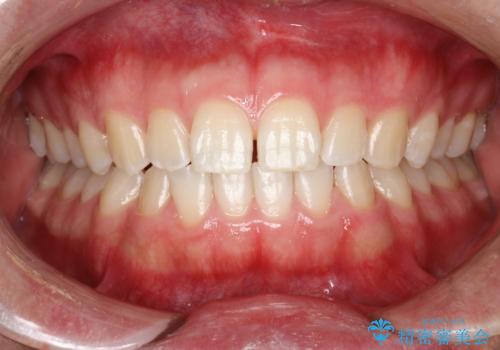

PMTCで前歯の着色・ステインを綺麗に

- 前歯の着色・ステインが歯磨きで取れないため綺麗にしてほしいとのことで来院されました。PMTC30分コースを行いました。

PMTCは、歯に付着した汚れを除去していくため、着色が気になる場合にも行うことができます。ご自身でのセルフケアだけで着色を落とそうとすると、逆に歯を傷つけてしまったり、精密に汚れを除去できないこともあります。また、日常生活で着色しやすい飲食物を避けたりすることはストレスに感じてしまったり、あまり現実的ではありません。